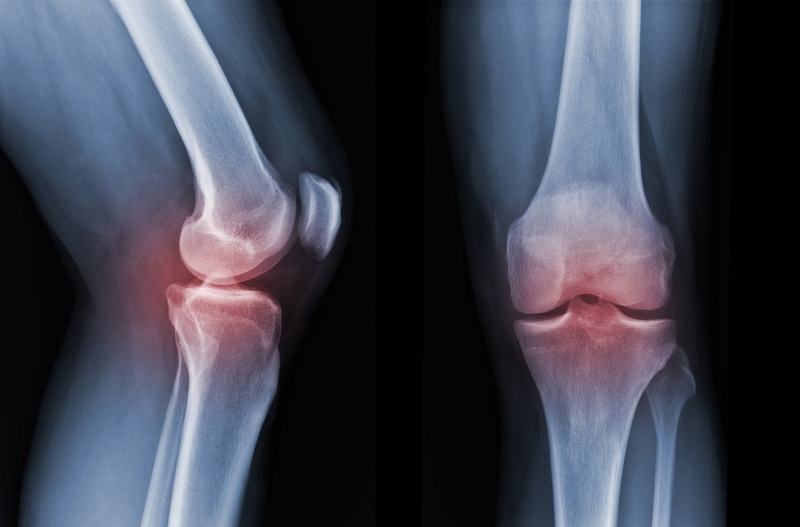

Hình ảnh chụp X quang khớp là căn cứ để bác sĩ đánh giá, chẩn đoán bệnh về khớp. Đây cũng là cơ sở để bác sĩ xác định phương pháp điều trị bệnh về khớp như điều trị nội khoa, điều trị ngoại khoa hoặc phẫu thuật thay khớp. Bác sĩ sẽ chỉ định chụp X quang khớp trong các trường hợp bệnh nhân bị đau đớn, khó chịu dai dẳng ở khớp mà không rõ nguyên nhân. Khảo sát hình ảnh có thể phát hiện các bất thường ở khớp vai, khớp cổ tay, khớp háng, khớp gối, khớp cổ chân.